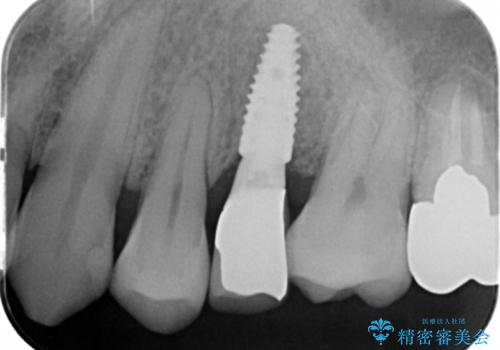

骨の厚みが不足していたため、インプラントの埋入と同時にソケットリフト(上顎骨に骨を増やす手術)を行いました。

インプラントの種類:ストローマン BLT

被せ物の種類:オールセラミッククラウン スタンダード